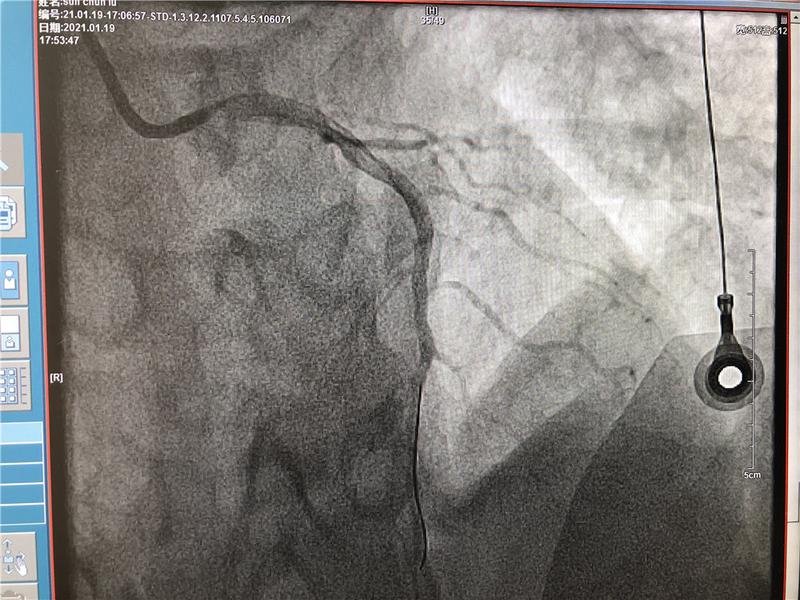

67歲的張大爺因“間斷胸痛半年,再發(fā)2天”入住心內(nèi)科,診斷冠心病、不穩(wěn)定型心絞痛。冠脈造影術(shù)提示左側(cè)冠狀動(dòng)脈血管嚴(yán)重狹窄。在與患者家屬充分溝通的基礎(chǔ)上,建議患者行冠脈搭橋或者支架植入術(shù)?;颊呒凹覍僮罱K選擇支架植入術(shù)。心內(nèi)科介入團(tuán)隊(duì)于患者左側(cè)冠狀動(dòng)脈血管植入支架一枚,整個(gè)手術(shù)僅歷時(shí)1小時(shí)15分鐘。術(shù)后患者病情穩(wěn)定,予以藥物繼續(xù)強(qiáng)化治療。出院時(shí),張大爺笑容滿臉,對(duì)自己第一個(gè)享受國家惠民政策感到榮幸,更對(duì)市人民醫(yī)院心血管內(nèi)科精湛醫(yī)療水平表示感謝。